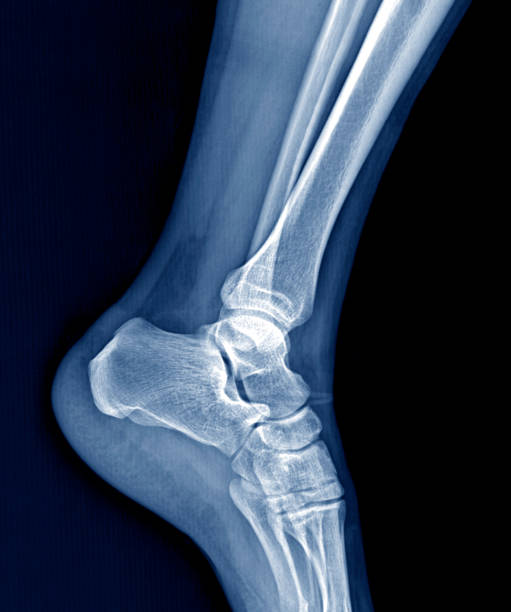

발뒤꿈치가 아픈 이유 2. 아킬레스건염

발뒤꿈치가 아픈 이유 두 번째는 아킬레스건염입니다. 아킬레스건염은 아킬레스건 부위가 반복적으로 미세한 손상을 입으면서 생기는 통증으로 이 역시 발뒤꿈치 통증을 유발합니다.

아킬레스건염 역시 뒤꿈치 혹은 발바닥에서 주로 통증이 느껴지며 특히 아킬레스건 부위가 부어오르며 움직임을 가져간 이후에는 종아리에서부터 발뒤꿈치까지 통증이 심하게 나타나고 이러한 증상이 지속되면 무플, 고관절, 허리에까지 무리가 갈 수 있기 때문에 족저근막염과 마찬가지로 빠른 치료를 받는 것이 중요합니다.